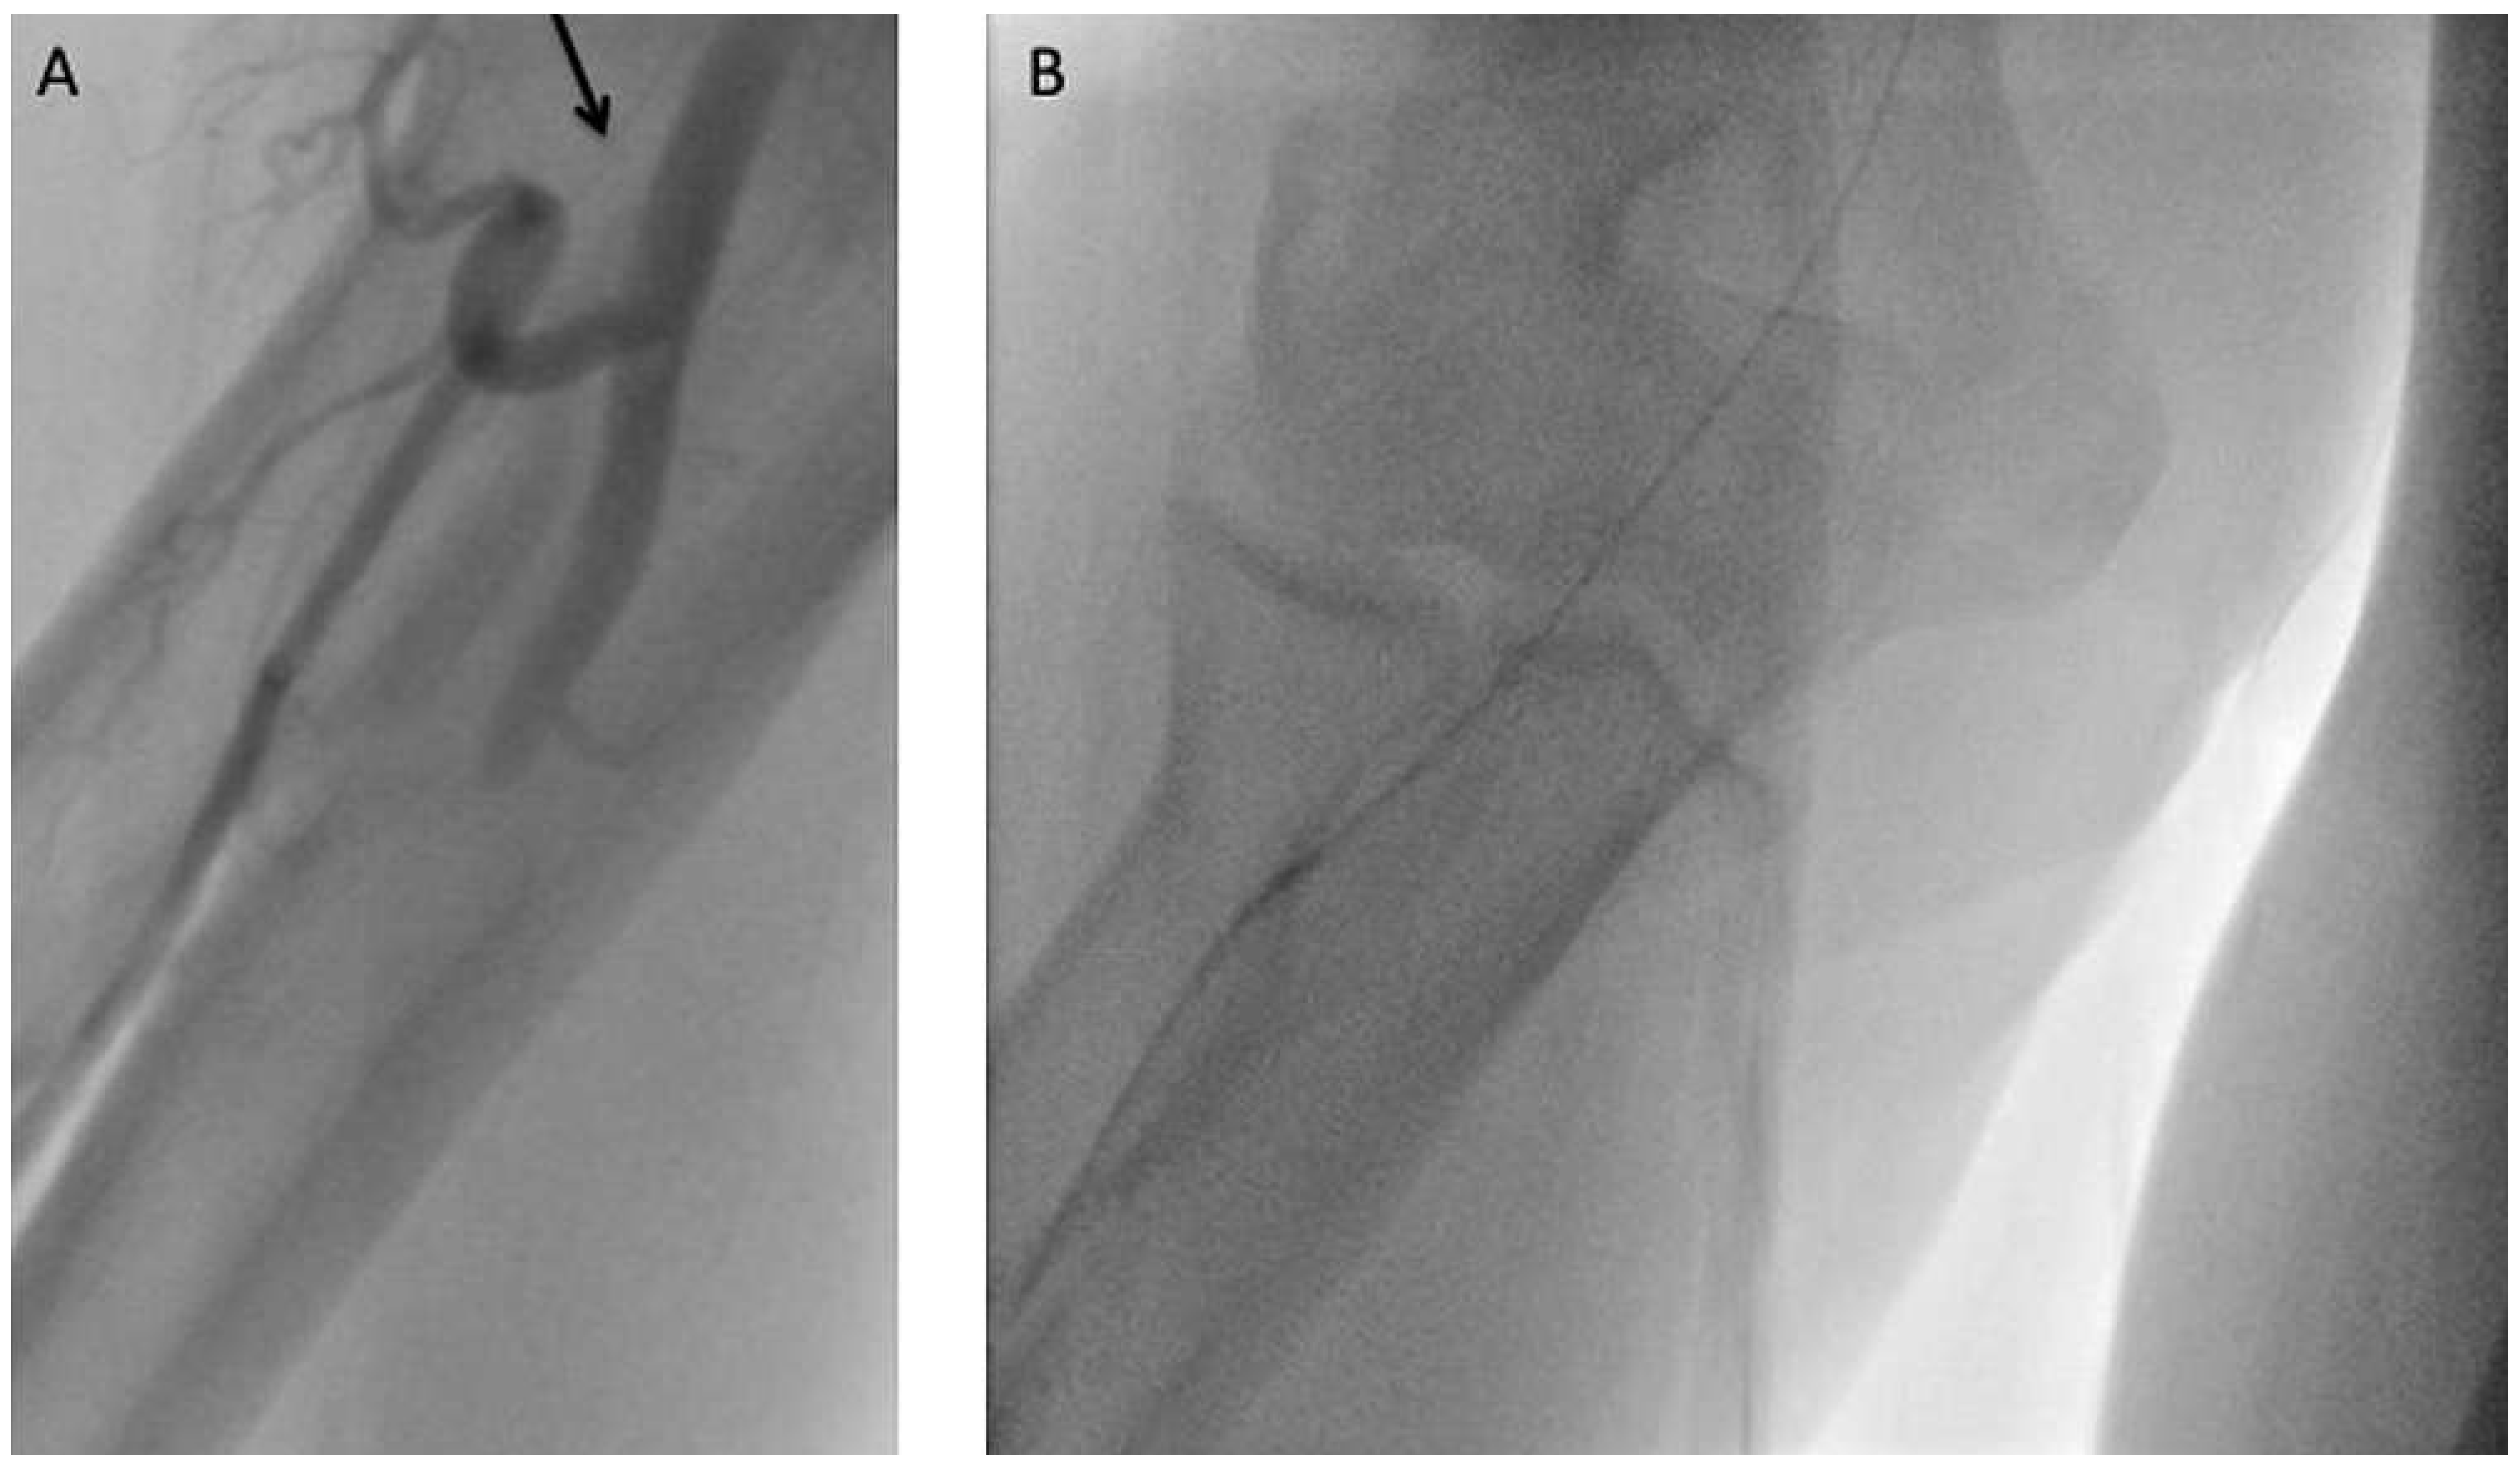

Radial artery tortuosity or loop

Subclavian artery tortuosity or loop